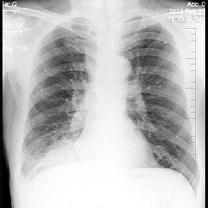

男性,62岁,咳嗽、胸痛一月,X线检查如图,最佳的诊断是 ( )A、右肺转移瘤B、右胸腔积液C、右下肺不张D、右肺癌E、右下肺炎症

问题 男性,62岁,咳嗽、胸痛一月,X线检查如图,最佳的诊断是 ( )

选项 A、右肺转移瘤 B、右胸腔积液 C、右下肺不张 D、右肺癌 E、右下肺炎症

答案 D